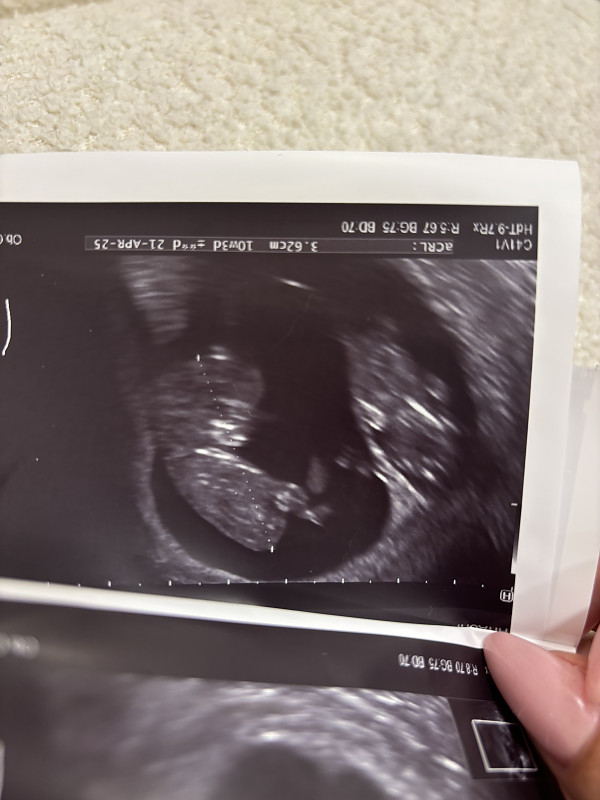

Buvau šiandien pas gydytoją. Du pipirai, dydžiai praktiškai vienodi, tik vizualiai atrodo A didesnis nei B, nes gimda gulsčia ir vienas aiškiai šonu matosi priekyje o kitas gale ir atsisukes priekiu ( nežinau, ar įžiūrėsite). Vienintelis neraminantis faktorius, kad B namelis daug mažesnis ir tai gali indikuoti kažkokias patologijas, ar ligas